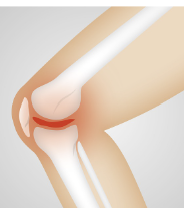

첫째, 골관절염입니다. 골관절염은 무릎 관절의 연골이 마모되어 뼈와 뼈가 마찰하는 상태로, 나이가 들면서 자연스럽게 발생할 수 있습니다. 골관절염은 체중이나 운동량, 유전 등에 영향을 받을 수 있으며, 통증과 강직감이 주된 증상입니다.

둘째, 류마티스 관절염입니다. 류마티스 관절염은 면역계의 이상으로 인해 무릎 관절에 염증이 생기는 자가면역질환입니다. 류마티스 관절염은 여성에게 더 흔하며, 젊은 연령대에서도 발생할 수 있습니다. 류마티스 관절염은 통증과 부기, 열감, 홍반 등이 나타납니다.

무릎 관절염은 무릎 관절에 염증이 생기게 되면서 무릎 부위가 붓고 따끔하게 느껴질 수 있습니다. 염증은 보통 활동 후에 심해지고, 아침에 일어나거나 오랫동안 앉아있으면 줄어듭니다. 염증은 무릎 관절에 액체가 축적되거나 연골 조직이 파열되어 발생할 수 있습니다.

무릎 관절염은 무릎 관절의 움직임을 제한하게 됩니다. 무릎을 굽히거나 펴는 것이 어렵고, 계단을 오르내리거나 앉았다 일어나는 것이 힘들어집니다. 또한 무릎이 삐걱거리거나 갑자기 멈추는 현상이 나타날 수 있습니다. 이러한 증상은 연골이 마모되어 뼈와 뼈가 서로 마찰하거나, 연골 조각이 관절 사이에 걸리거나, 인대나 근육이 손상되어 발생할 수 있습니다.